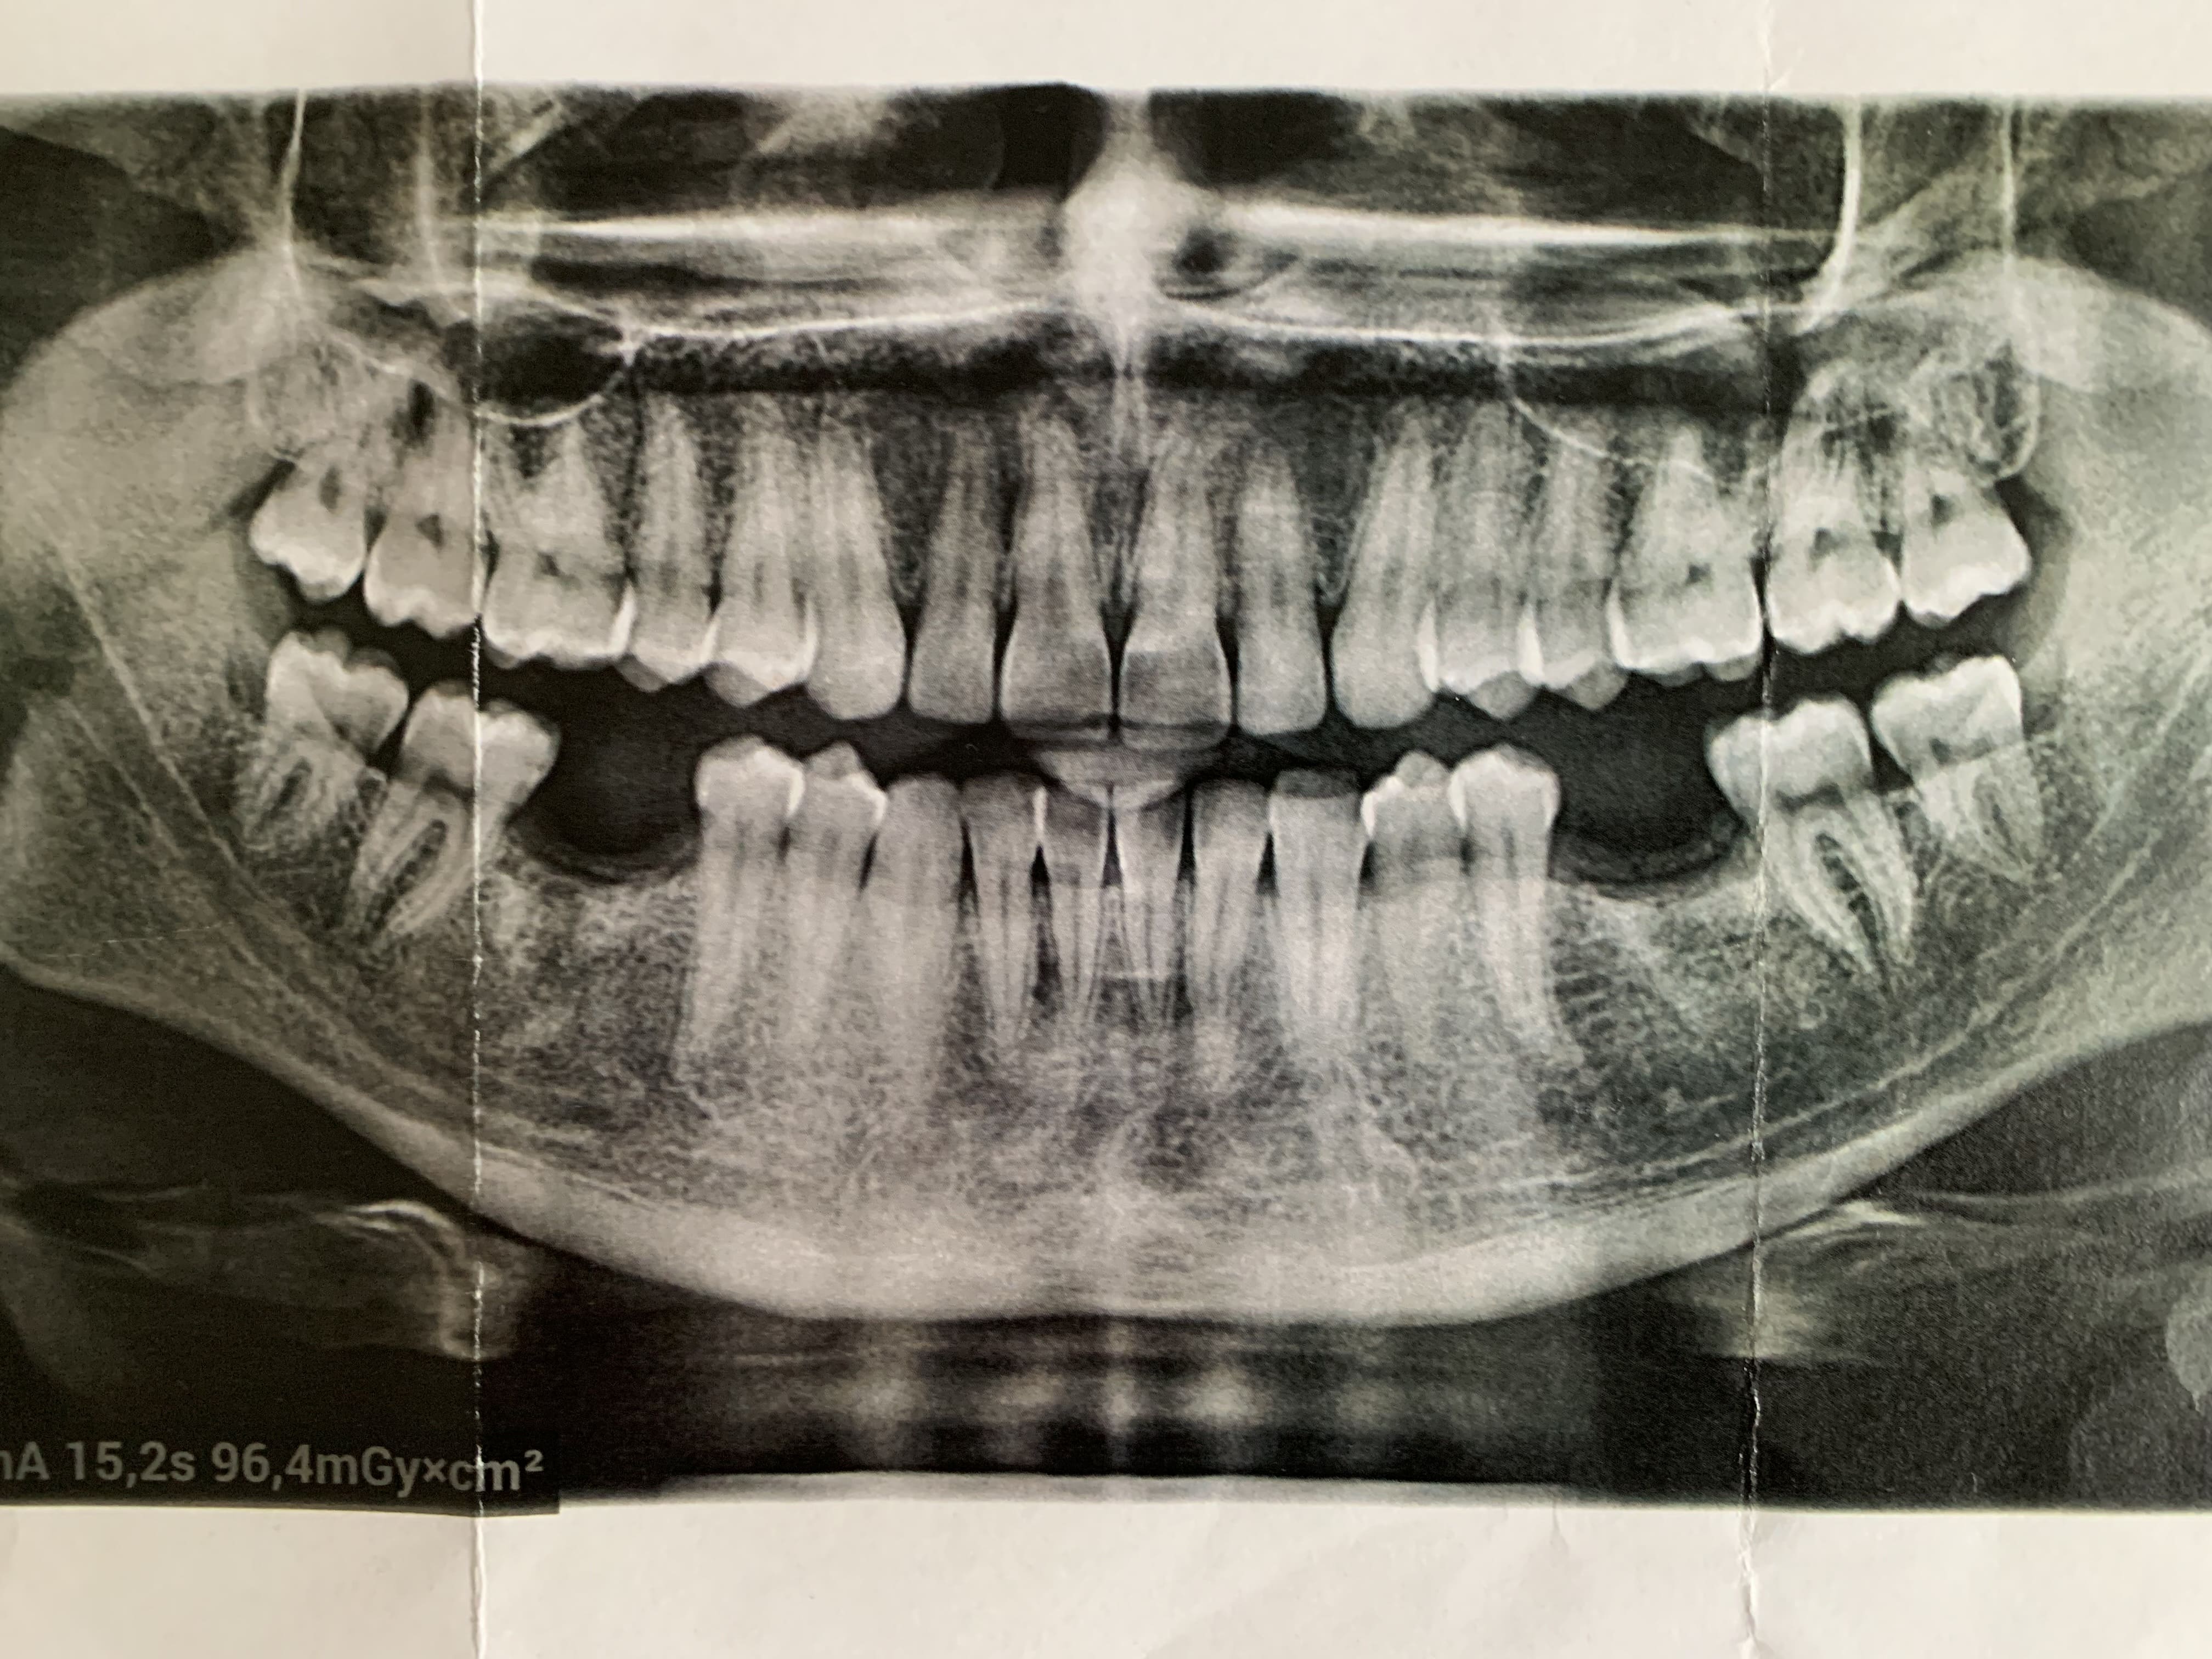

Patient de 27 ans. Se plaint de douleurs sourdes dans la zone 38... Il n'arrive pas à situer exactement le source de la douleur mais me dit que c'est la 38 qui est en cause. Douleurs qui irradient vers oreille, cou et même épaule.

Ce que je ne comprends pas, c'est que visuellement il n'y a aucun signe d'infection et /ou inflammation dans la zone. Tout est sain.

Pas un petit tassement alimentaire entre 37.38 ?

Les contacts n'ont pas l'air très serrés.

Bon après, pano papier...

Il peut y avoir une atteinte de furcation, une 3 d apporte souvent la réponse. Sinon sonder en vestibulaire dans la furcation pour voir si ça reproduit les symptomes. Il peut y avoir fêlure d’une crête marginale auquel cas il y aurait douleur à la mastication et au froid…

Il y a une image bizarre en arrière de l'apex de la 28.

Idem sur 18.

Odontomes?

Une synalgie est possible 28/38.

Appuie avec ton index en AR de la 28 (en haut à gauche) pour rechercher une éventuelle douleur.

ODF mésialise.

On vire 18.28

Et

qu il ait perdu les 2 6 alors qu il est jeune et que les autres dents soient intactes

Que les canines soient plus petites que les PM

Vous trouvez ça normal ?

Comment peut-on dire que tout est sain alors qu'il manque deux dents très importantes dans l'équilibre fonctionnel. C'est normal que les points de contact sautent et qu'il y ait du tassement alimentaire, mais ce n'est qu'une conséquence.

Je rejoins plutôt Dentarue: bourrage alimentaire entre les dents ou plus probablement dans une pseudo poche en distal de la 8, une espèce de péricoronarite chronique, que le patient bien intentionné t'empêche de constater en brossant bien avant de venir te voir ce qui fait qu'il n'a plus aucun symptôme.

Certes les sagesses sont sorties mais en distal c'est loin d'être ok.... Elles seraient pas un tantinet sous muqueuses?

Ça plus le point de contact élargi...

Faudrait les virer ainsi que les antagonistes et proposer de remplacer les 6 absentes.